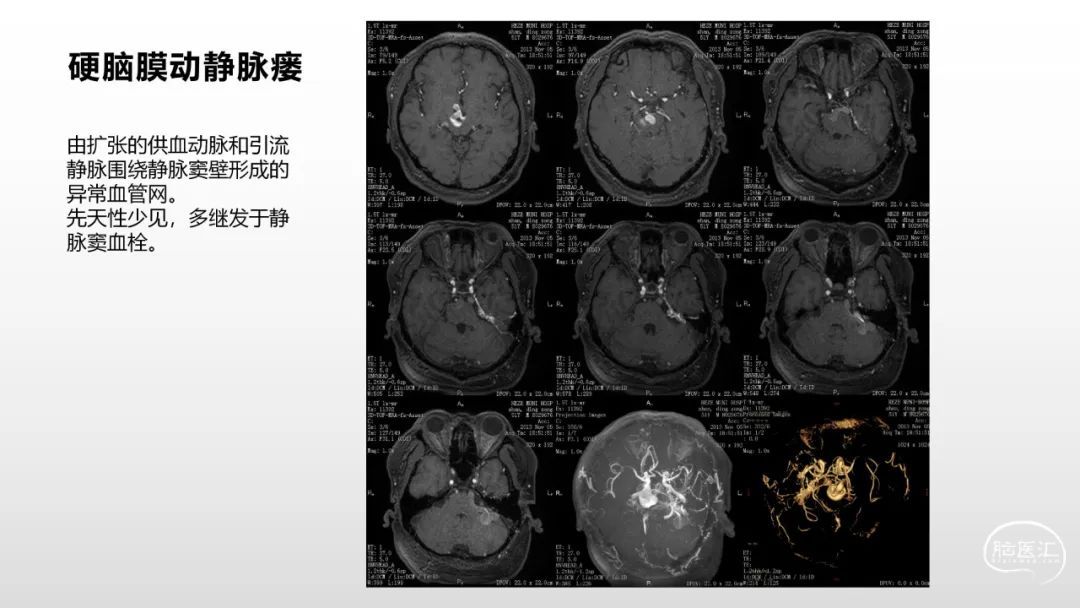

颅脑影像诊断基础知识讲座:脑膜病变